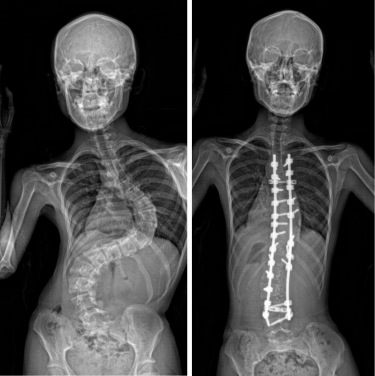

AIS is a common skeletal disorder, characterised by a lateral curvature of the spine exceeding 10 degrees, which affects 3.5% of adolescents aged between 10 and 18 in Hong Kong1. It worsens during puberty and can result in various complications including impaired cardiopulmonary functions, shortness of breath, back pain, uneven shoulders and hips, and overall poor cosmesis. These physical challenges can impact the social and psychological well-being of the affected individuals. Currently, treatment options are limited to bracing and invasive surgery after the condition develops. Preventive interventions remain unavailable, and its etiology is uncertain.

AIS Cases

Among the patients involved in the study, Miss Lam and Miss Law were particularly instrumental in the success of the research. Both of them experienced severe scoliosis during their teenage years, and underwent surgical correction of their scoliosis deformities at the Duchess of Kent Children’s Hospital. Subsequently, 61% of Miss Lam’s family and 50% of Miss Law’s family also developed scoliosis, several of whom required surgical intervention. This SLC6A9 mutation carries an autosomal dominant pattern, which was found in the many involved members of their families.